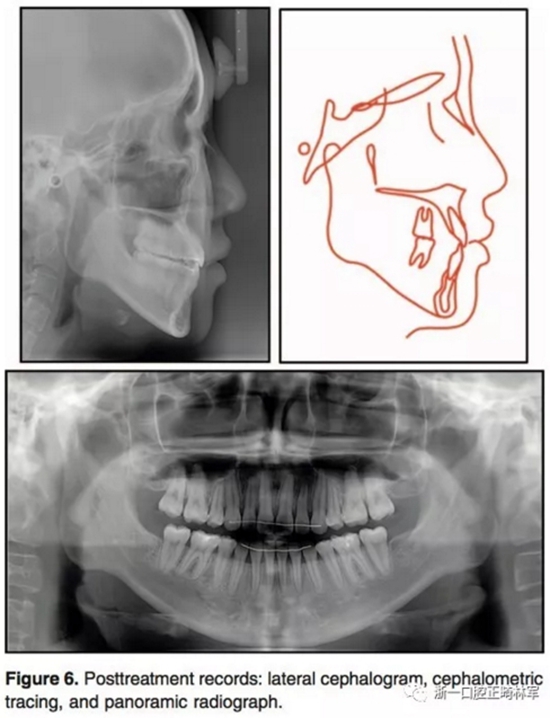

1年的保持,示咬合和面型保持良好。治療后和保持后的重疊像示上下切牙輕微唇傾,導(dǎo)致覆蓋有所增加。上下第一磨牙的位置變化微乎其微。

9.jpg